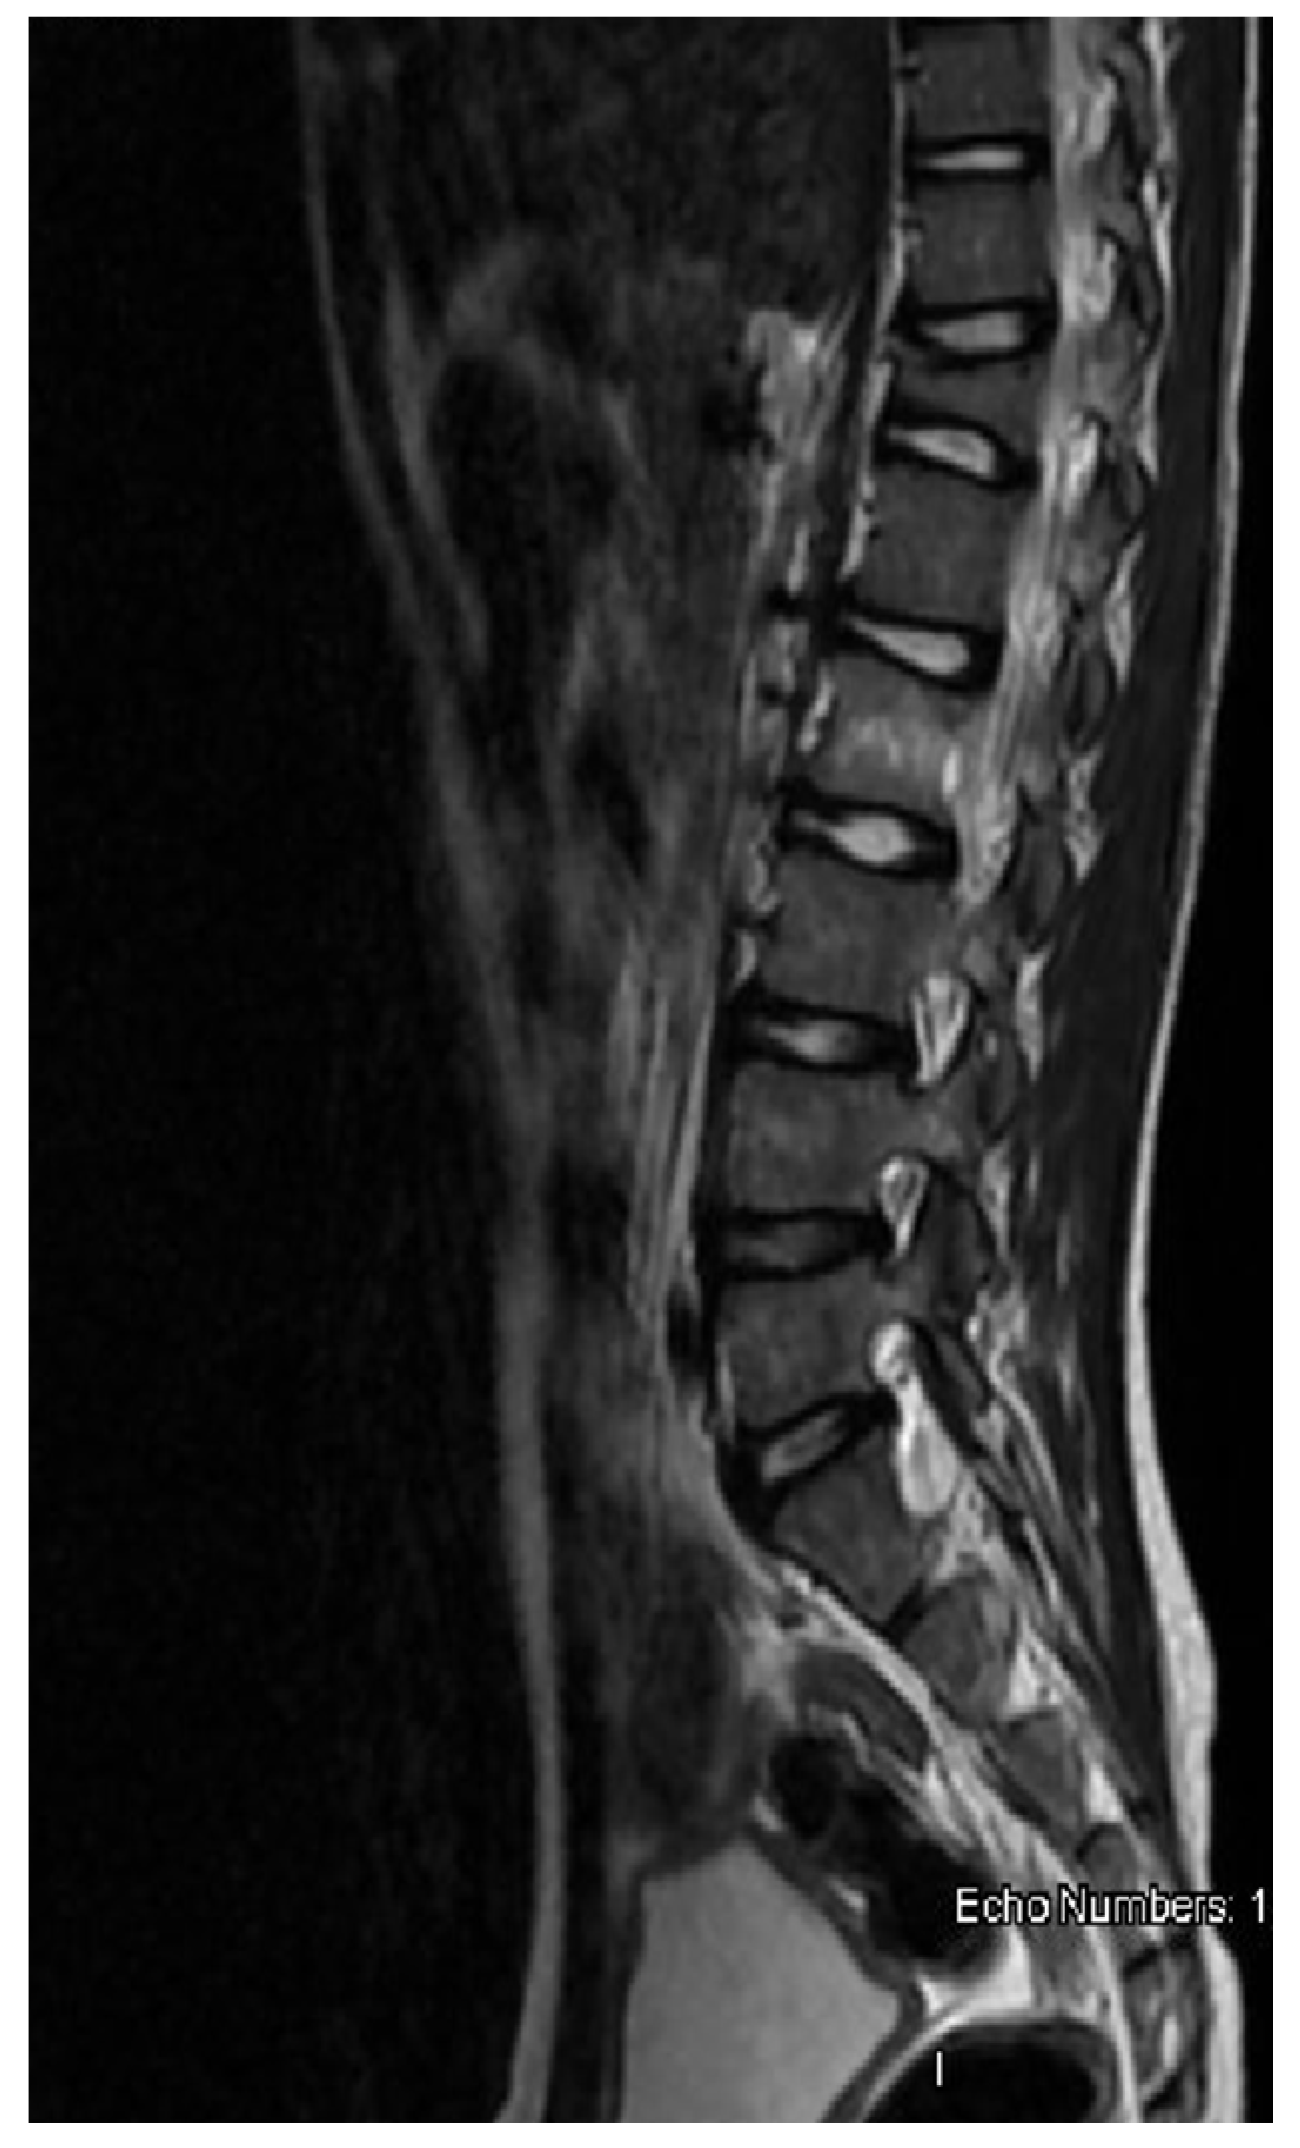

A previously healthy 9-year-old boy came to our attention for back pain, lasting more than 2 months, with no other symptoms; he had been treated with physiotherapy and anti-inflammatory drugs. On clinical examination, the boy was well-appearing, complaining of moderate back pain at the lumbar level. Complete blood count, lactate dehydrogenase, uric acid, C-reactive protein, and erythrocyte sedimentation rate were in the normal range. Spine magnetic resonance imaging (MRI) showed a signal alteration at the D12-L2 level (with a wedge-shaped D12 body) characterized by hypointensity at T1-weighted and hyperintensity at T2-weighted sequences; furthermore, an abnormal tissue involving medullary canal and neural foramina was appreciated at the D11-L1 level (Figure 1). Cerebral, thorax, and abdominal CT were of normal appearance. The boy underwent an open biopsy, and the histological diagnosis was ALCL, CD30+, ALK+, EMA+, perforin+, associated with numerous histiocytes CD68PGM1+. Positron emission tomography/computed tomography (PET-CT) showed high fluorodeoxyglucose (FDG) uptake at D11-L2 level, with spinal cord involvement. Lumbar puncture revealed the presence of 66 T-lymphoblasts/μL in the cerebrospinal fluid (CSF) and bone marrow aspirate was positive for NPM-ALK transcript, detected by qualitative RT-PCR. The patient was treated with six courses of chemotherapy according to the AIEOP LNH-97 protocol for ALCL, high-risk group, with CNS involvement (Table 1) [3]. MRD in bone marrow and peripheral blood was negative just after the first course of chemotherapy. PET-CT, performed after the second chemotherapy block, showed a complete metabolic response, confirmed also at the end of treatment. Spine MRI performed 2 weeks after stop-therapy demonstrated complete disappearance of both D12-L1 lesions and tissue proliferation in the D11-L1 region, with the persistence of mild signal alteration, without any contrast enhancement, at the L2 level only (Figure 2). During the follow-up, the boy was also monitored by the analysis of MRD in peripheral blood every month for the first three months, then every two months up to one year from the stop-therapy: NPM-ALK transcript was never detected. The patient is in clinical, radiological, and molecular remission at 12 months after the end of treatment.

Figure 1. Spine MRI at onset: wedge-shaped D12 vertebral body and abnormal tissue proliferation with involvement of medullary canal at L1-L2 level.